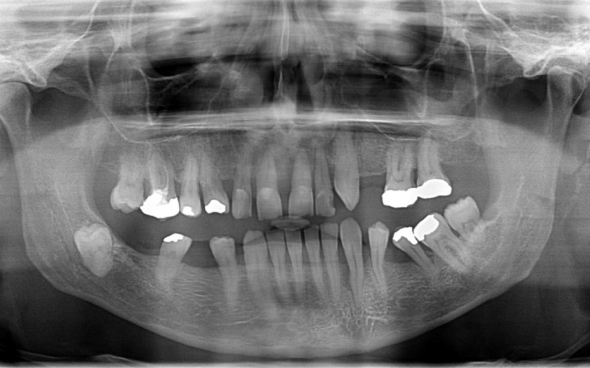

Metallkeramische Oberkiefer- und Unterkiefer-Vollbrücken

Der 48 jährige österreichische Patient erschien an unserer Zahnklinik zu einem Beratungstermin, wo eine Röntgenaufnahme und ein Kostenplan für metallkeramische Vollbrücken im Ober- und Unterkiefer mit insgesamt 25 Kronen erstellt wurden.